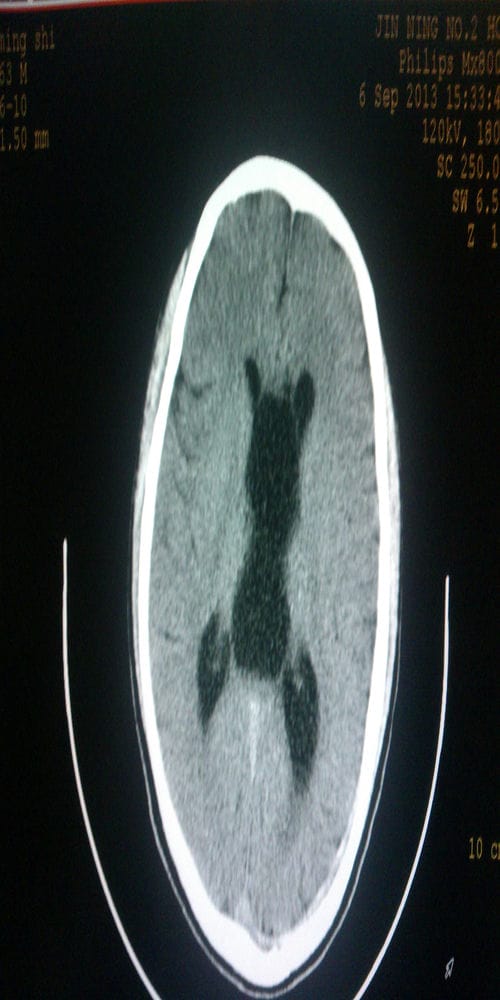

1.下列哪种方法为颅脑疾病诊断的基本方法: ( )

A.脑室造影 B.计算机体层 C.头颅平片 D.医学影像 E.脑血管造影